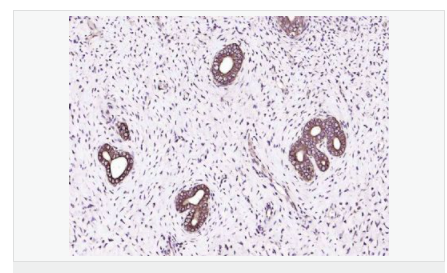

| 產品應用 | WB=1:500-2000 ELISA=1:5000-10000 IP=1:20-100 IHC-P=1:100-500 IHC-F=1:100-500 IF=1:100-500 (石蠟切片需做抗原修復) not yet tested in other applications. optimal dilutions/concentrations should be determined by the end user. |

| 免 疫 原 | KLH conjugated synthetic peptide derived from human IGF-1:49-100/195 |